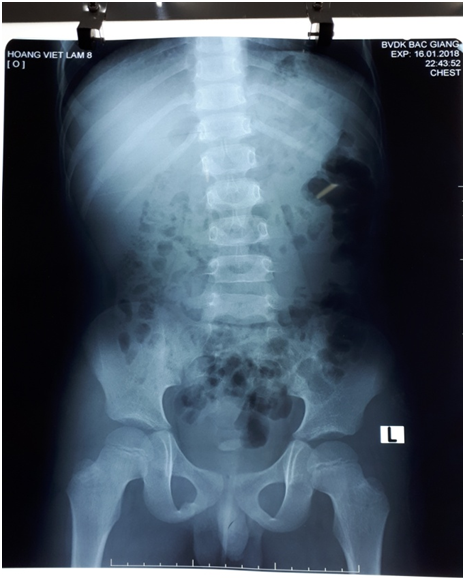

X-quang bụng không chuẩn bị có thể được thực hiện để kiểm tra vị trí của ống thông niệu quản hoặc để kiểm tra vị trí và theo dõi sự phát triển của sỏi thận. Tuy nhiên, để có chẩn đoán ban đầu về bệnh sỏi tiết niệu, chụp X quang thường kém nhạy và ít đặc hiệu hơn chụp CT và thiếu chi tiết giải phẫu, vì vậy đây không phải là phương pháp được lựa chọn.